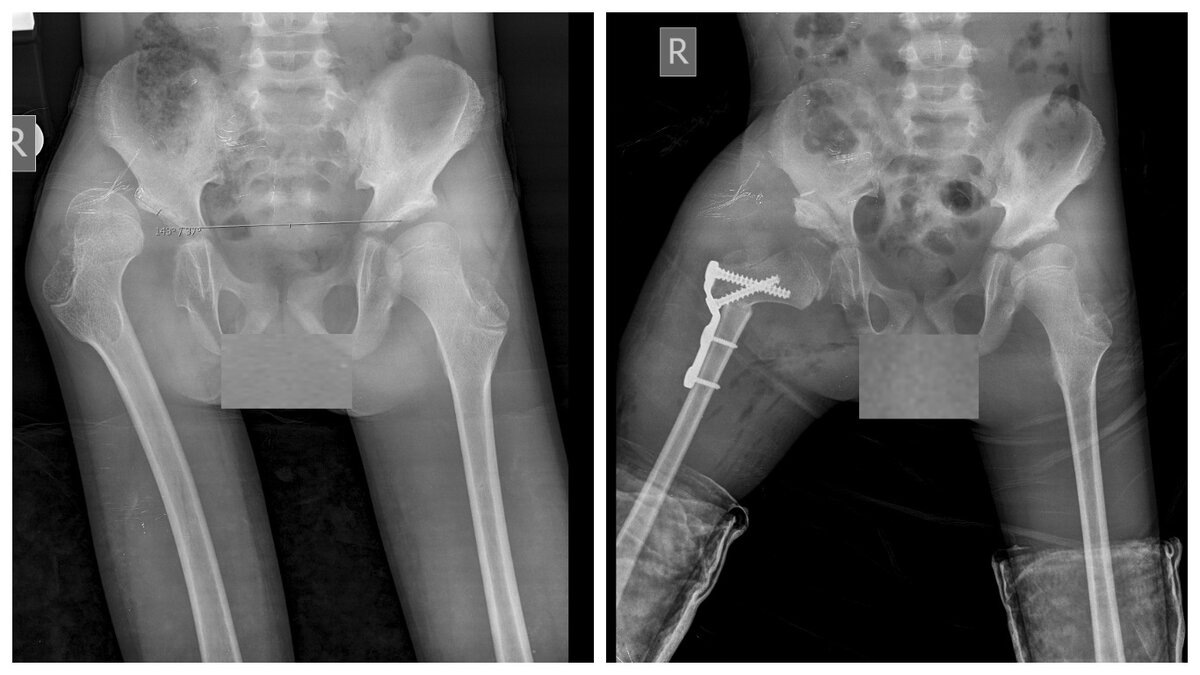

Реконструктивная операция на правом тазобедренном суставе по поводу вывиха и дисплазии вертлужной впадины: деротационно-варизирующая остеотомия в сочетании с  ацетабулопластикой по San Diego